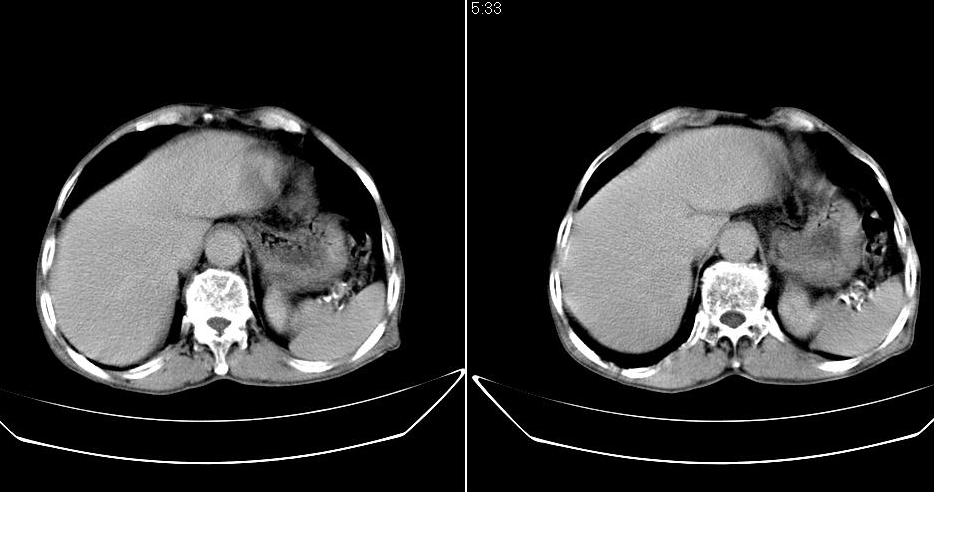

男,76岁,上腹部疼二天来就诊,彩超提示肝左叶占位,随后做上腹部ct平扫,今天做上腹部ct增强扫描,手工推药,效果不好,请谅解。

肝左叶s4肿块强化形式大概是:慢进慢出,逐渐强化----考虑血管瘤/腺瘤?{动脉期应更提前扫}。

肝右叶前段hcc

1)肝右叶前段低密度灶,不排除肝癌可能;建议查afp。2)右肾上极囊肿。

肝内胆管积气扩张,胆囊增大,肝右前叶低密度灶,逐渐强化,一元论,胆系感染,局限性肝脓肿;右肾囊肿。

考虑肝s4段肝脓肿可能?未排除肝癌。右肾上极囊肿。